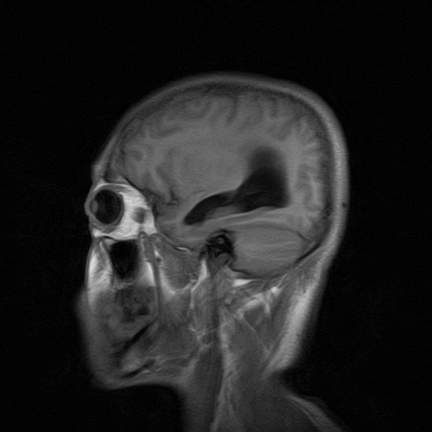

标题: MRI2064:少见病例。男性52,视力下降多年。 [打印本页]

标题: MRI2064:少见病例。男性52,视力下降多年。

四脑室区见混杂信号占位影,脑室系统扩张明显,临近结构显著受压称位,患者52岁,多考虑室管膜瘤可能性大

考虑第四脑室室管膜瘤并阻塞性脑积水。

考虑第四脑室室管膜瘤并梗阻性脑积水;部分性空蝶鞍;左侧上颌窦粘膜下囊肿。

考虑第四脑室室管膜瘤【血供丰富血管母细胞瘤可能】并梗阻性脑积水;部分性空蝶鞍;左侧上颌窦粘膜下囊肿。

比较典型的脉络丛乳头状瘤并脑积水,鉴别小脑蚓部血管母细胞瘤。